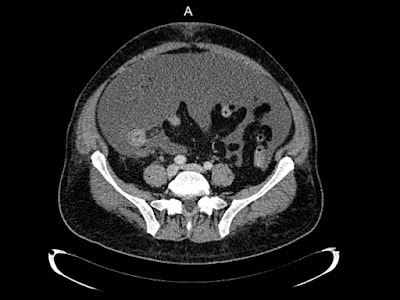

Dolor en hipocondrio derecho

Femenina de 31 años